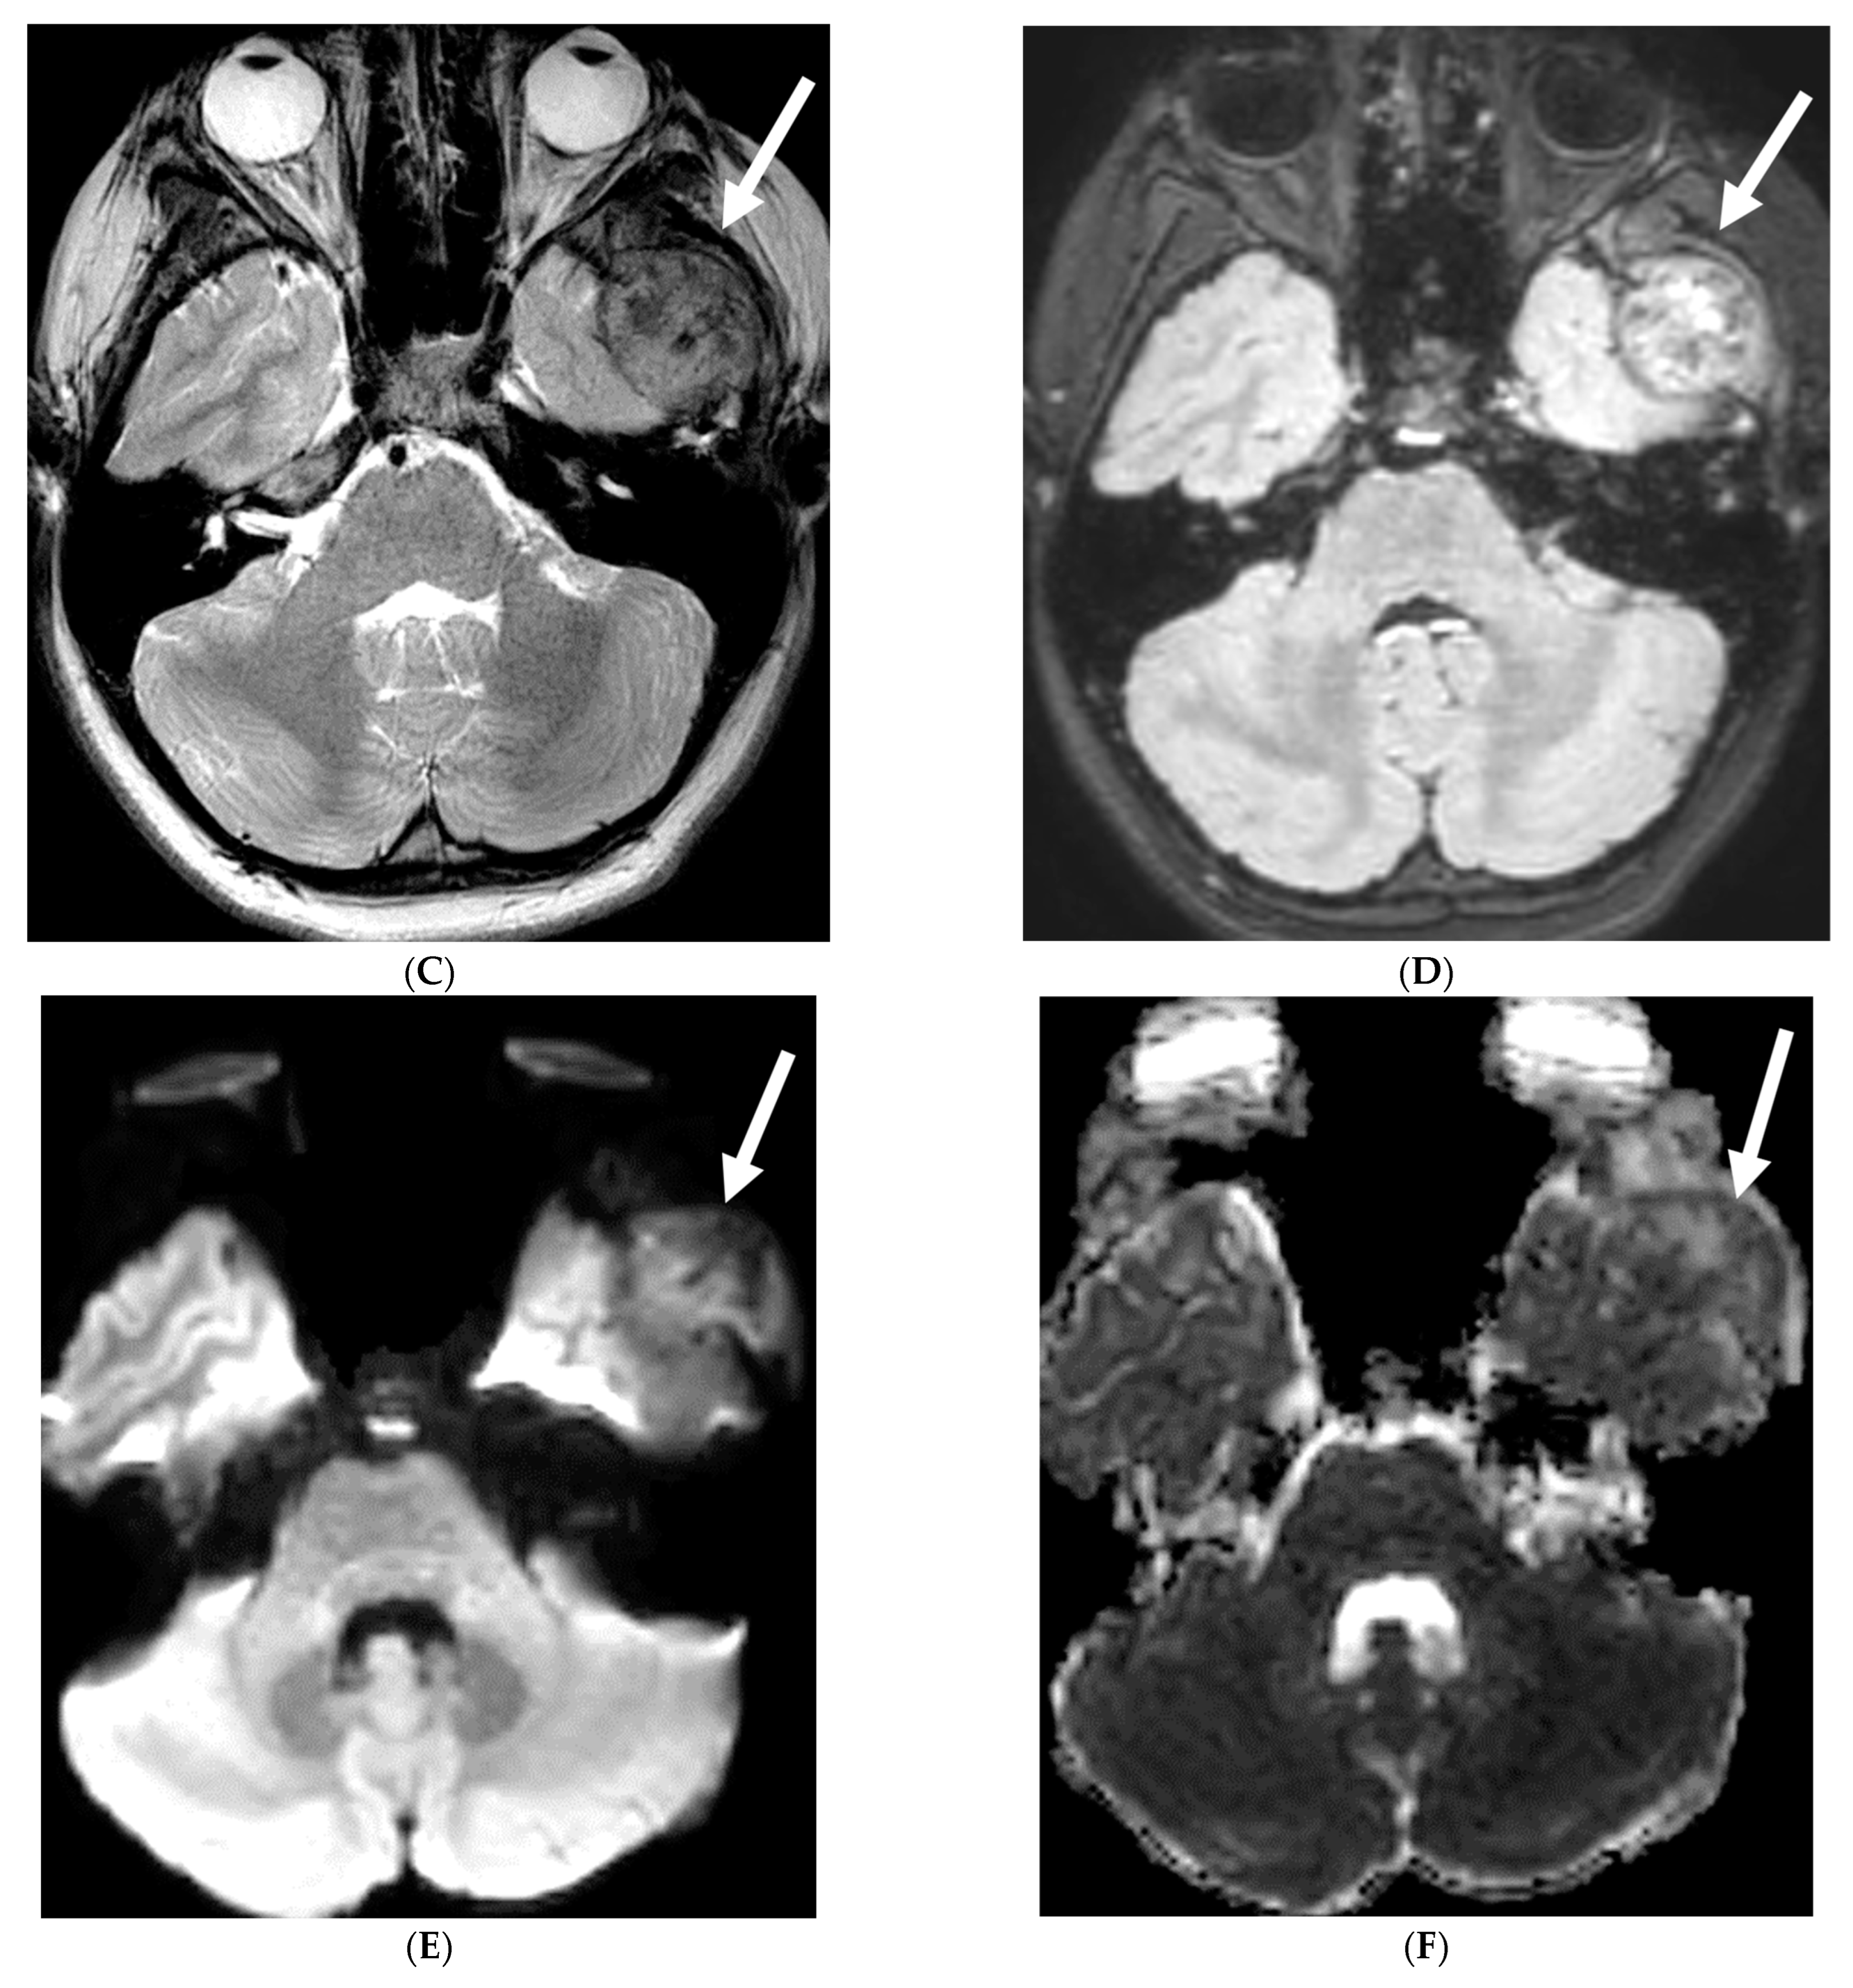

3.9. Alk-Positive Histiocytosis

ALK-positive histiocytosis (APH) is a rare, non-Langerhans cell histiocytosis that can involve the nervous system, including the meninges. While the disease is often seen in infants and young children, it can occur at any age [68]. Neurologic involvement usually presents as seizures, ataxia, headaches, and vomiting [69]. Imaging findings on CT include iso-dense or slightly hyperdense nodules/masses [70]. On MRI, lesions demonstrate isointense or slightly hypointense signals on T1-weighted, isointense or hypointense signals on T2-weighted, with moderate homogeneous focal or smooth ring enhancement [71]. Meningeal enhancement (Figure 10F) can appear segmental and be particularly prominent along the cauda equina [71]. Restricted diffusion is also commonly seen (Figure 10 and Figure 11) [69].

Figure 10.

Axial T2 (A), sagittal T1 post contrast (B), Sagittal T2 (C,E) and sagittal T1 post contrast (D,F): 20-month-old boy with 2 months of losing developmental milestones and 1 month of emesis, fatigue and dehydration. Ventriculomegaly with transependymal fluid is noted (black arrows). There is posterior fossa leptomeningeal nodular enhancement extending into the upper cervical spine (curved white arrows). Extensive nodular enhancement along spinal cord (dashed white arrows) with cord edema demonstrated in the entire cord (white arrows).

Figure 11.

3 weeks follow up: Post contrast sag T1 (A) and axial FLAIR (B), Axial T2 (C), sagittal T2 (D), Post contrast sagittal T1 (E) and PET/CT (F): Leptomeningeal nodular enhancement along posterior fossa, suprasellar and spinal cord (curved arrows) has significantly increased. There is also new/increased signal abnormality in the brain stem and cord (white arrows). Hypermetabolic spine disease is demonstrated on PET/CT. No osseous involvement is identified on the PET scan. Pathology: Diffuse CNS ALK (Anaplastic Lymphoma Kinase)-Positive Histiocytosis. Bone marrow biopsies, US abdomen and skeletal survey negative for extracranial/extraspinal disseminated disease.